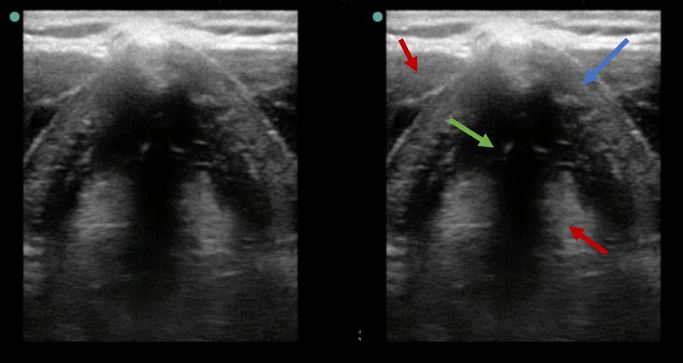

En la figura 2 se aprecia el corte transversal del cuello a la altura del cartílago tiroides. Puede identificarse el cartílago tiroides como una estructura hipoecogénica en forma de herradura (flecha azul). También vemos estructuras musculares hipoecoicas heterogéneas (flechas rojas) y una estructura ligamentosa hiperecogénica fina (flecha verde), correspondientes a los ligamentos de las cuerdas vocales (glotis abierta).